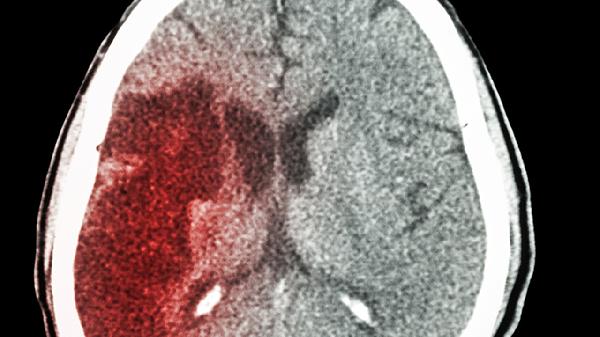

早产儿脑室内出血是后天性脑积水的常见原因,出血后形成的血块可能阻塞脑脊液循环通路。这类患儿有明确的围产期缺氧或产伤史,急性期需使用维生素K1注射液止血,后期根据病情选择脑室腹腔分流术或腰大池腹腔分流术。